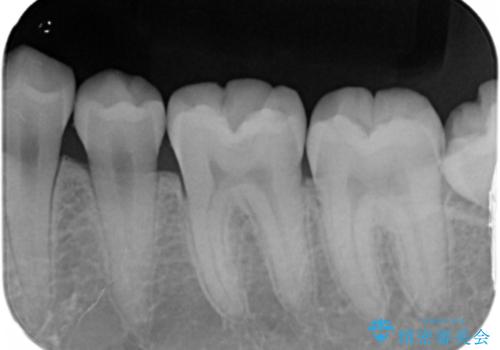

- 10年以上ぶりに歯科に来院された患者です。

口腔内・レントゲン写真からう蝕が見られたので治療を勧めたところ、自費治療を希望されたのでセラミックインレーにて治療を行いました。

左下6番のカリエス除去を行ったところ、深くまで削る必要があったため、CR裏層をした上でセラミックインレー形成をしました。